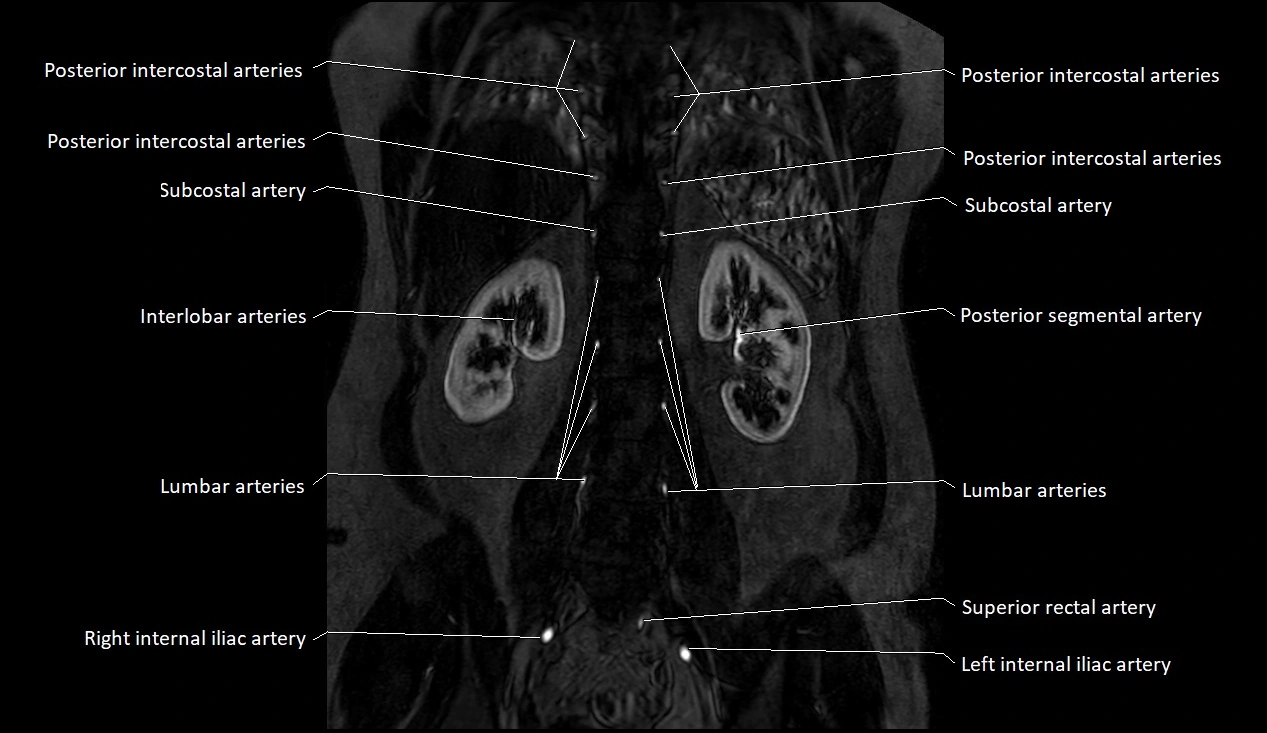

MRA (Magnetic Resonance Angiography):

• Contrast-enhanced MRA provides high-resolution imaging of the aorta and its branches

• Allows 3D reconstruction of visceral, parietal, and terminal branches

• Excellent for evaluating aneurysm size, dissection flap, stenosis, or preoperative planning

• Non-invasive alternative to conventional angiography

MRI images

image